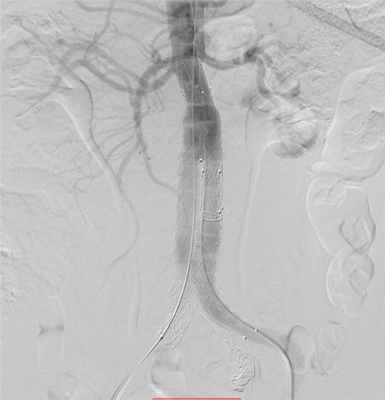

Наиболее точную информацию о наличии аневризм дают такие методы диагностики, как компьютерная томография, магнитно-резонансная томография, ангиография.

Специалисты ФГБУ «ФЦССХ им. С.Г. Суханова» Минздрава России (г. Пермь) применяют эндоваскулярные технологии в лечении аневризм аорты. Такие операции проводятся в специальных рентгеноперационных, главным их отличием от «большой» хирургии является малая травматичность процедуры и быстрое восстановление пациента. Через небольшой прокол на бедре выше и ниже расширенного участка аорты устанавливается стент-графт – каркасная трубка, которая будет выполнять функцию аорты с полным восстановлением кровотока и изоляцией аневризмы.

Имплантация стент-графта брюшной аорты

Для диагностики расслоения аорты используются такие методы исследования, как электрокардиография (ЭКГ), рентгенография, ультразвуковые исследования (эхокардиография – ЭхоКГ, в частности чреспищеводная, ультразвуковое исследование брюшной полости), магнитно-резонансная томография, компьютерная томография с внутривенным введением контрастного вещества. Ангиография аорты (аортография) – эталонный метод диагностики расслоения аорты.